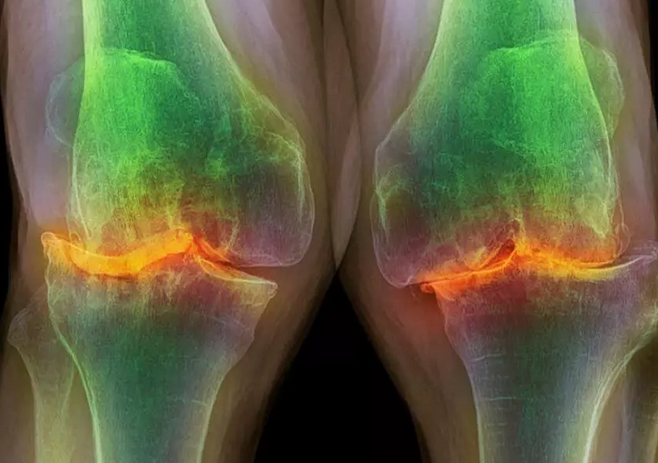

وی ادامه داد: آرتروز بیشتر در زانو و ستون فقرات دیده میشود به طوری که آرتروز زانو و کمر شایعتر از مفاصل دیگر است. معمولاً با افزایش سن و در اثر فشارهایی که در طور زندگی به غضروف مفصلی وارد میشود ضخامت این غضروف کمتر میشود در اصطلاح به این کم شدن ضخامت غضروف مفصلی آرتروز میگویند.

عبداللهی به نشانههای وجود آرتروز در افراد اشاره کرد و گفت: اولین علائم ایجاد درد است یعنی فرد هنگام نشستن، بالا و پایین رفتن از پله و پیاده روی، احساس درد میکند. نشانه بعدی ایجاد تورم در مفصل است. علاوه بر آن اگر آرتروز پیشرفت کرده باشد فرد در انجام فعالیتهای روزمره با مشکلات فراوانی مواجه خواهد بود به عنوان مثال فرد به دلیل وجود آرتروز شدید زانو دیگر نمیتواند راه برود و مجبور است مسافتهای کمتری را پیاده راه برود. پس میتوان نتیجه گرفت اولین علائم و نشانهها درد، تورم در مفصل و محدودیت حرکت است.